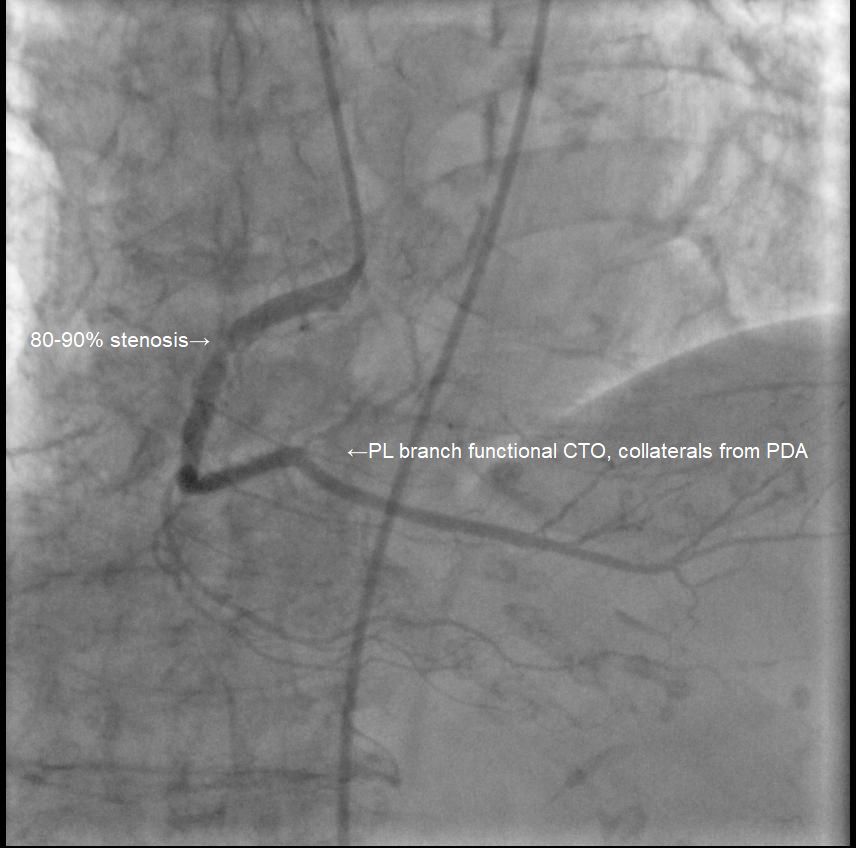

Coronary angiography showed significant stenosis:

RCA 80-90% (proximal to mid), and PL branch functional CTO, collaterals from PDA, indicating multi-vessel disease.

Left main 50-60%,

RCA 80-90% (proximal to mid), and PL branch functional CTO, collaterals from PDA, indicating multi-vessel disease.